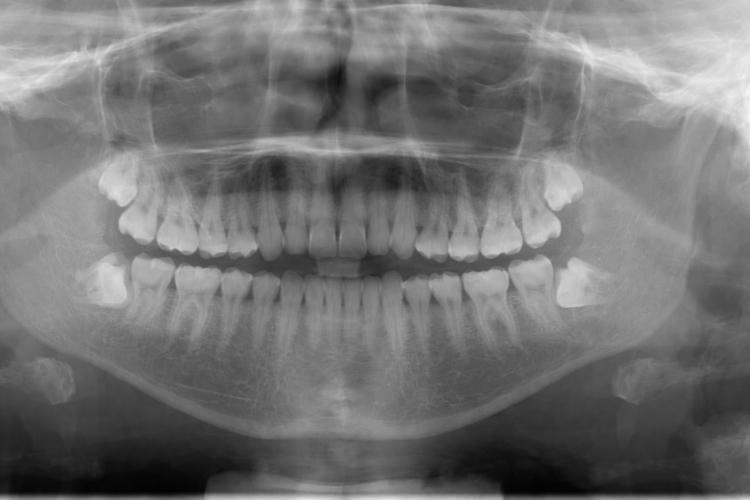

- Treatment is carefully planned using diagnostic imaging.